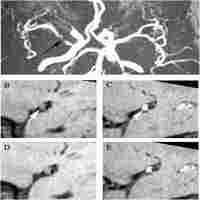

| Abstract | Capsular warning syndrome (CWS) is rare (1.5% of TIA presentations) but has a poor prognosis (7-day stroke risk of 60%). Up to date, the exact pathogenic mechanism of CWS has not been fully understood. We report the clinical presentations and high-resolution MRI (HR MRI) findings of two cases with capsular warning symptoms. Case 1 was a 63-year-old man with a history of hypertension with recurrent episodes of left hemiparesis and dysarthria lasting 10 ~ 30 minutes. Case 2 was a 54-year-old woman with repetitive episodes of transient left hemiparesis and dysarthria lasting about 10 minutes. Capsular infarctions on DWI were demonstrated in the territory of a lenticulostriate artery in both 2 patients. HR MRI disclosed atherosclerotic plaques on the ventral wall of the MCA where enticulostriate arteries were arisen from, although traditional digital subtraction angiography showed normal. Aggressive medical therapy with dual antithrombotic agents and statin was effective in these two cases. Our HR MRI data offer an insight into the pathophysiology of CWS which might be caused by atherosclerotic plaque in non-stenotic MCA wall. HR MRI might be a useful modality for characterizing atherosclerotic plaques in the MCA and detecting the pathophysiology of the CWS. |